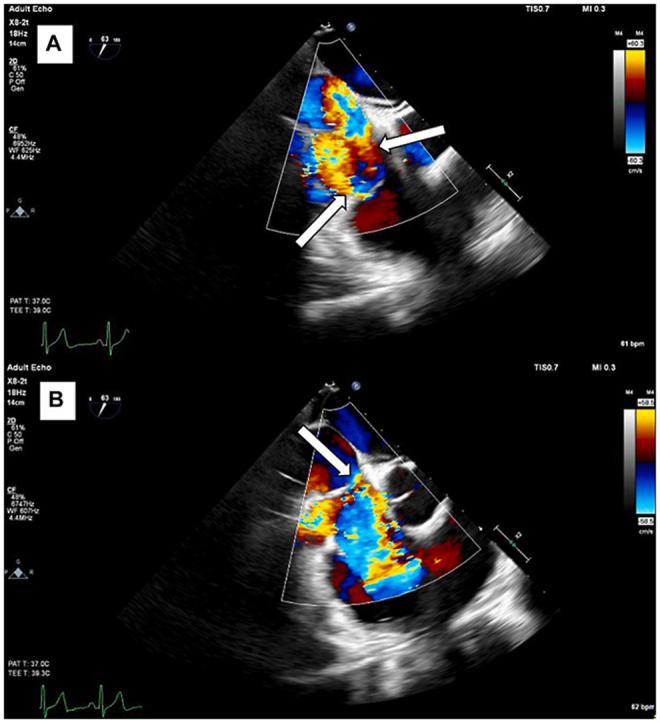

Cor Triatriatum Dexter Associated With a Dysplastic Tricuspid Valve.

• Cor triatriatum dexter results from persistence of the right valve of the sinus venosus. • A 3D evaluation can help differentiate CTD from other congenital abnormalities. • Treatment options for CTD include surgery, first line, or percutaneous resection.

• 右三房心由静脉窦右瓣持续存在引起。

• 三维评估有助于将右三房心与其他先天性异常区分开来。

• 右三房心的治疗选择包括手术(一线治疗)或经皮切除术。